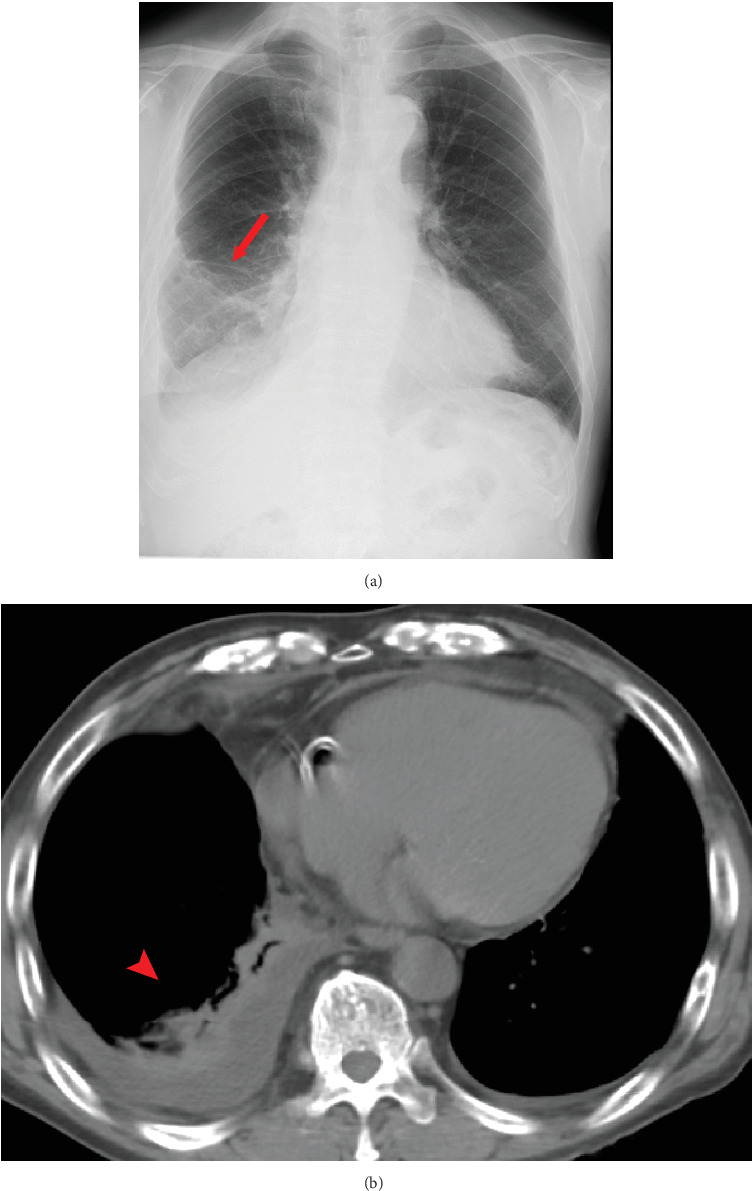

我们描述了两例经历了严重的多重免疫相关不良事件(irAEs)、治疗中断和类固醇治疗的患者。尽管存在这些挑战,但它们取得了超出预期的显著抗肿瘤效果。多种肿瘤显示免疫检查点抑制剂的抗肿瘤作用可能与irae的强度相关,但对恶性胸膜间皮瘤(MPM)的研究很少报道。我们的两个病例表现出比平常更强的irae。这两个病例仍然表现出完全缓解(CR)或接近CR部分缓解,表明irAEs与MPM抗肿瘤作用之间存在相关性。

We describe two patients who experienced serious multiple immune-related adverse events (irAEs), treatment interruption, and steroid administration. Despite these challenges, they achieved a remarkable antitumor effect beyond the expected. Various carcinomas demonstrated a possible correlation between the antitumor effect of immune checkpoint inhibitors and the intensity of irAEs, but few studies report on malignant pleural mesothelioma (MPM). Our two cases exhibited much stronger irAEs than usual. These two cases still demonstrated a complete response (CR) or near CR partial response, indicating a correlation between irAEs and the antitumor effect in MPM.